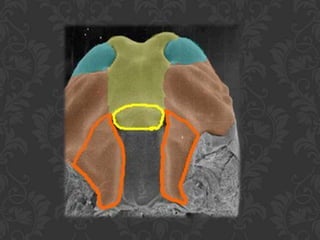

DESENVOLVIMENTO DO PALATOA partir de 3 PRIMÓRDIOSProcesso palatino mediano (Palato primário) –porção anteriorProcessos palatinos laterais (Palato secundário) –porção posterior, mais extensa• O palato secundário cresce durante a 7ª. Semana    • Crescimento medial e fusão no plano mediano adiante    do processo palatino mediano    • Concomitante, o septo nasal cresce caudalmentee    funde-se ao palato    • O canal incisivo definitivo marca a separação do    crescimento entre os palatos primário e secundário

DESENVOLVIMENTO                   DO PALATO PROCESSO PALATINOMEDIANO    (PALATO PRIMÁRIO)PORÇÃO ANTERIORPROCESSOS PALATINOS LATERAIS(PALATO SECUNDÁRIO) PORÇÃO POSTERIOR MAIS EXTENSA

DESENVOLVIMENTO DO PALATOApartir de 3 PRIMÓRDIOSProcesso palatino mediano (Palato primário) –porção anteriorProcessos palatinos laterais (Palato secundário) –porção posterior, mais extensa• O palato secundário cresce durante a 7ª. Semana • Crescimento medial e fusão no plano mediano adiante do processo palatino mediano • Concomitante, o septo nasal cresce caudalmentee funde-se ao palato • O canal incisivo definitivo marca a separação do crescimento entre os palatos primário e secundário